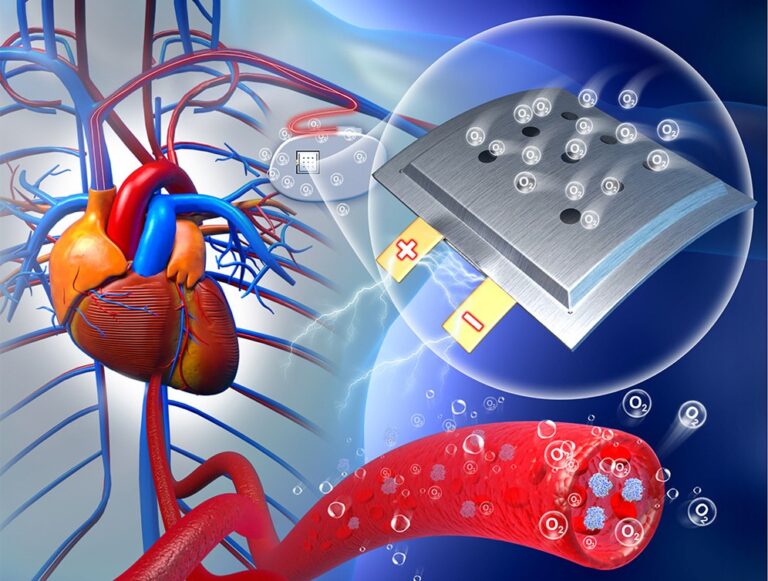

Reménysugár rengeteg betegnek: maga a szervezet lehet a beültetett eszközök akkumulátora

Kínai kutatók állatkísérlete reményt nyújt arra, hogy a jövőben a mostaninál jóval hosszabb ideig ne kelljen cserélni a szervezetbe ültetett orvosi eszközök akkumulátorait. A működtetéshez szükséges energiát ugyanis maga a szervezet adja.